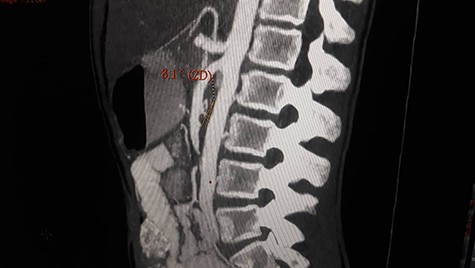

Patient underwent contrast enhanced CT scan for abdomen and pelvis, which revealed severely dilated stomach and significant dilatation of the duodenum up to the level of the distal third part, abrupt narrowing (transition zone) was seen just anterior to the AA and posterior to the SMA (Figs. 1 and 2) as well as significant reduction of the aortomesenteric angle (measuring 8.1°) and aortomesenteric distance measuring about 7 mm (Fig. 1).

Contrast enhanced CT scan abdomen and pelvis (sagittal view) (axial view) showing duodenal compression between the aorta and superior mesenteric artery.